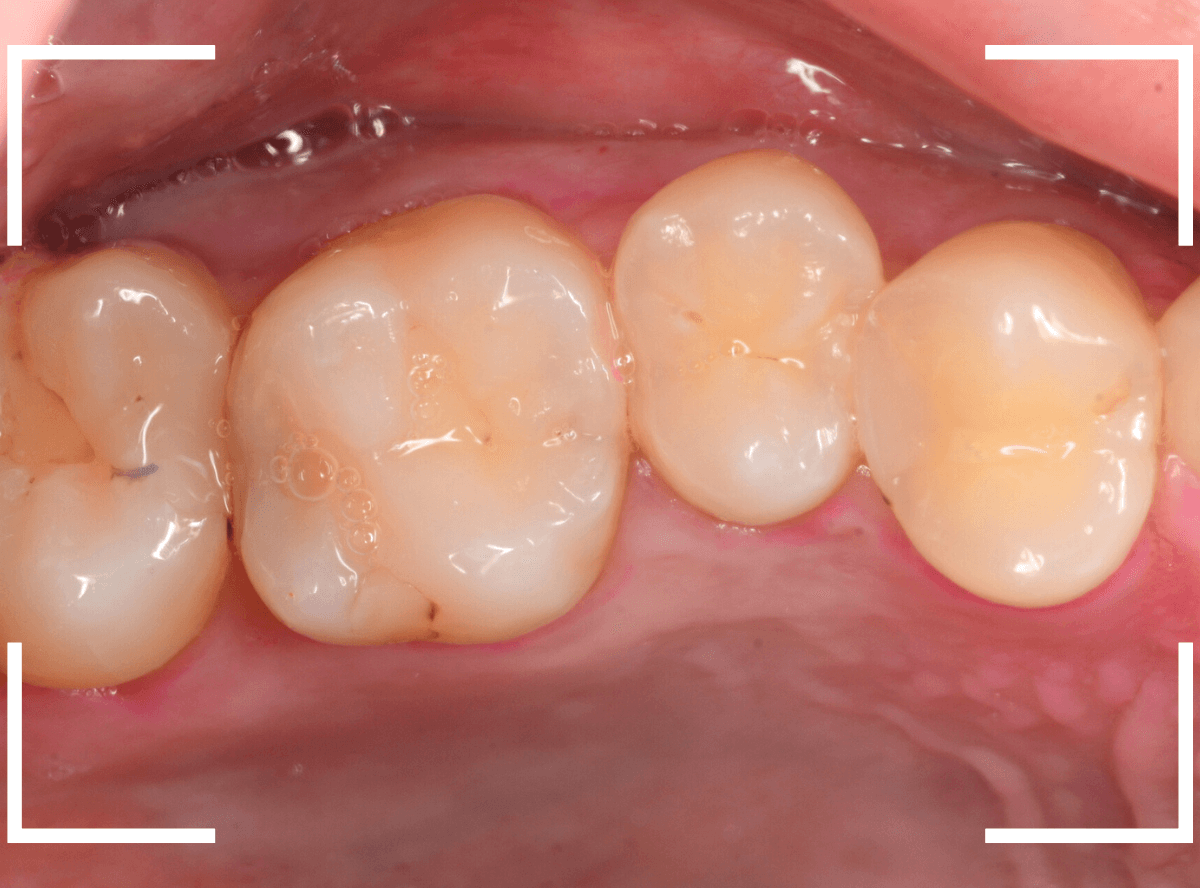

Case.1 奥歯のスキマが大きな虫歯!

他の歯の治療目的で来院された患者さんです。

全体検査の際、ちょっとこの歯、アヤシイなと思いましたが、確証はありませんでした。

(この写真で改めて見ると、かなりアヤシイと思いました)

レントゲン写真で確認すると、かなり大きな虫歯でした。

後日、改めて時間をお取りして、麻酔をかけて治療を開始です。

歯の表面を少し削ると、ボロッと虫歯が出てきました(>_<)

歯と歯の間の虫歯は、大抵は両方の歯に広がっている事がほとんどです。

今回のケースも、隣の歯まで、虫歯は広がっています。

最終的には、かなり神経に近いところまで虫歯が進んでいました。

もう少し遅かったら、危なかったと思います。

他の歯の治療で来院された事が、幸運でした。

しばらく経過観察した後、特に症状がありませんでしたので、隣の歯をレジンで治療後、ジルコニア・インレー(70,000円(税込み/2024年1月現在))で治療することにありました。

治療後の写真です。

特に症状もなく、審美性も高く治療することができました♪